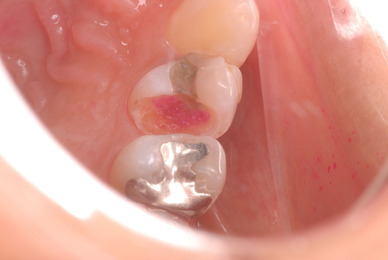

歯周病の疑いで東京のかなり遠方の方が来院されました。

驚くべきことですが、定期検診は受けていたそうです。しかしながら歯周病の指摘は受けたことがないそうです。

何故か?定期検診が虫歯のチェックのみになり、又肝心の歯周病の検査や歯周病の部分の予防や治療のためのブラシの使い方などを学んだ事がないのです。

本当に患者さんのことを考えると憂鬱になります。歯周病が悪化すると殆ど回復は無理だからです。